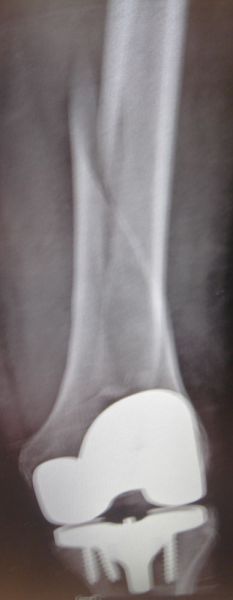

5. Periprosthetic fracture of the left femur in a 75-year-old male with a total knee arthroplasty.

Treatment: Open reduction internal fixation

I. Anteroposterior x-ray of the femur shows the periprosthetic fracture II. Post-surgery, x-ray shows the metal work and the reduction of the fracture. The arthroplasty was stable therefore there was no need in this stage for the replacement of the prothesis